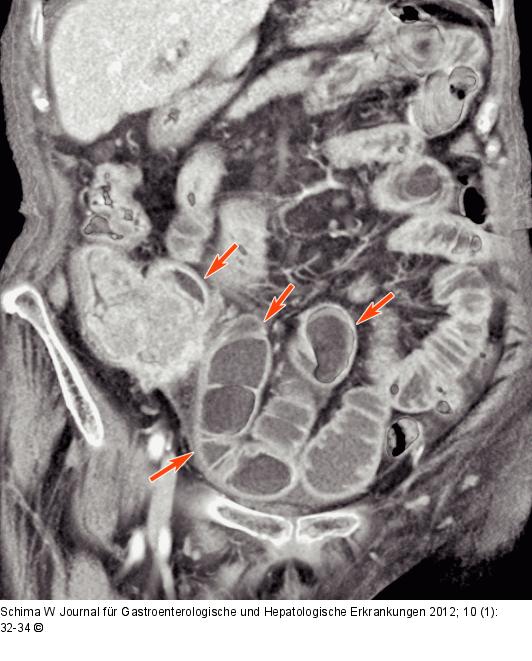

Abbildung 2c: Dilatation - Dünndarmschlingen Die 3D-Rekonstruktion (VRT) zeigt anschaulich die Dilatation der Dünndarmschlingen (Pfeile) aufgrund der Obstruktion. |

Abbildung 2c: Dilatation - Dünndarmschlingen

Die 3D-Rekonstruktion (VRT) zeigt anschaulich die Dilatation der Dünndarmschlingen (Pfeile) aufgrund der Obstruktion. |